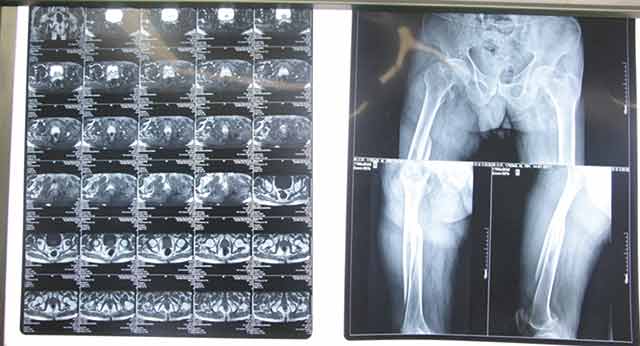

▲術(shù)前

經(jīng)過骨科專家團(tuán)隊(duì)的詳細(xì)查體以及相關(guān)拍片、CT等輔助檢查,韓大爺被診斷為右側(cè)的股骨干骨折合并同側(cè)粗隆間骨折。通過和病人及家屬耐心細(xì)致地溝通,韓大爺收住我院骨科。經(jīng)過詢問病史,了解到韓大爺有胃出血及疝修補(bǔ)手術(shù)史約10余年,并伴有老年高血壓病史,年事已高、病情復(fù)雜,需要制定更為詳細(xì)的診療方案。骨科主任楊連海及副主任孫守全立即組織科內(nèi)討論,充分與患者家屬進(jìn)行溝通、以得到家屬的認(rèn)可,細(xì)致而縝密地結(jié)合病人的個(gè)體情況定制手術(shù)方案。由于病情復(fù)雜,麻醉科主任修冬云在手術(shù)前親自看望韓大爺?shù)纳眢w狀況,認(rèn)真分析評估手術(shù)的風(fēng)險(xiǎn)程度,排除手術(shù)禁忌,選擇合適的麻醉方式。經(jīng)過積極的術(shù)前準(zhǔn)備,孫守全副主任擇期在硬膜外麻醉下完成了髖部骨折+同側(cè)股骨干骨折髓內(nèi)重建釘?shù)膬?nèi)固定手術(shù),手術(shù)過程非常順利,骨折復(fù)位基本達(dá)到解剖復(fù)位。術(shù)后經(jīng)過預(yù)防感染、鎮(zhèn)痛、預(yù)防下肢深靜脈血栓等治療,韓大爺恢復(fù)的非常好,沒有出現(xiàn)感染、血栓等并發(fā)癥,而且傷口甲級愈合。